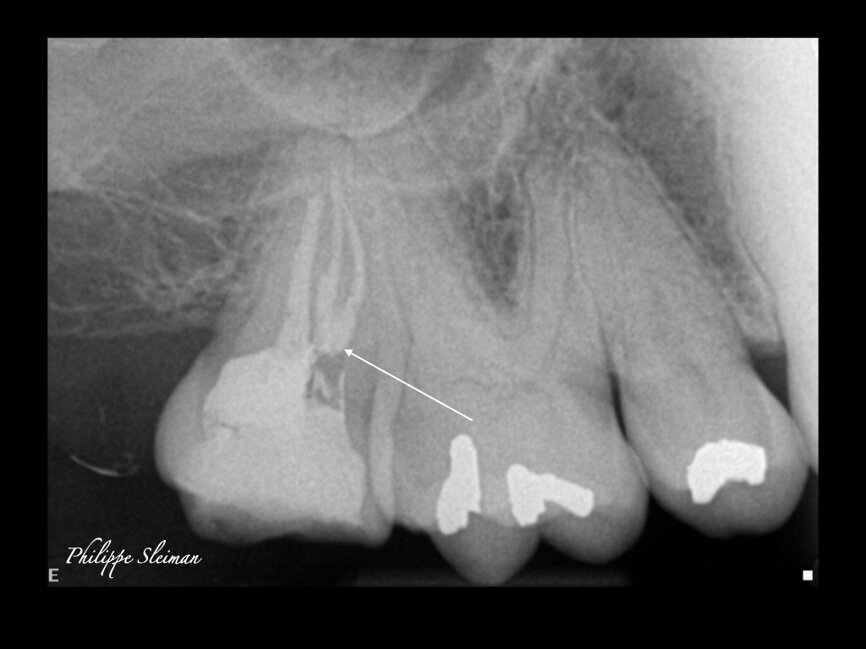

Case 3

Irreversible pulpitis was causing this patient a great deal of pain. When examining the preoperative radiograph (Fig. 9), I saw doubled periodontal ligament on the mesial root, which clearly indicated a second canal in this root. The opening of the second mesiobuccal canal was very tight and very small; nevertheless, it had a separate exit.

The immediate postoperative radiograph in Figure 10 does not show it, but an image at a further 15° angle would clearly show the independent exit of the second mesiobuccal canal. A micro-CT scan of a similar anatomy—as we can never find two identical anatomies—is illustrated in Figure 11.